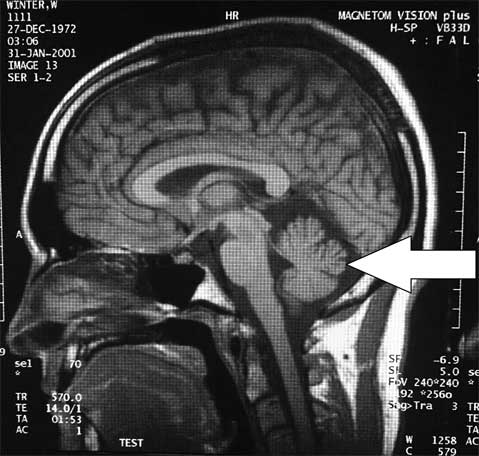

Все мои пациенты говорили, что внутри очень шумно, усиливается клаустрофобия и в целом чувствуешь себя некомфортно. Я был сильно разочарован. Что меня действительно впечатлило, так это размер моего мозжечка – до странного маленький. Следующим утром я прикрепил свой МРТ-снимок в читальном зале врачей-неврологов. У нас была такая традиция – прикреплять необычные снимки, чтобы другие врачи могли написать рядом с ними свои догадки и теории. Практически все, кто не заметил мое имя на снимках, написали «церебеллярная гипоплазия», то есть нехарактерно маленький мозжечок. Странно, но мой мозжечок (часть мозга, отвечающая за координацию мышц; на фото указан стрелкой) был немного маловат, как вы можете видеть. А большинство тех, кто все-таки увидел мое имя, предположило «атрофию яичек». Умники.

Рис. 1. Мой мозг, версия 2001